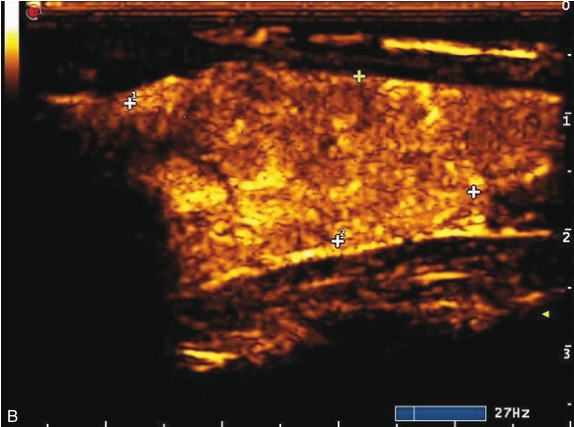

甲状腺右叶上部结节超声造影后早于周围组织开始出现增强,达峰时呈偏低增强表现,边界不清,范围未见明显扩大,之后快速消退,晚期呈明显低增强,结节旁甲状腺被膜增强完整,见图1-9-6、ER1-9-3。

造影后结节内呈不均匀偏低增强表现,增强边界不清,增强晚期快速消退。

图1-9-6 甲状腺髓样癌超声造影图

A.动脉早期;B.达峰时;C.增强晚期

髓样癌体积较小时与乳头状癌的鉴别存在困难,内部丰富血流是髓样癌的主要特点,超声造影表现为中等偏低增强,与乳头状癌明显的低增强表现有别。